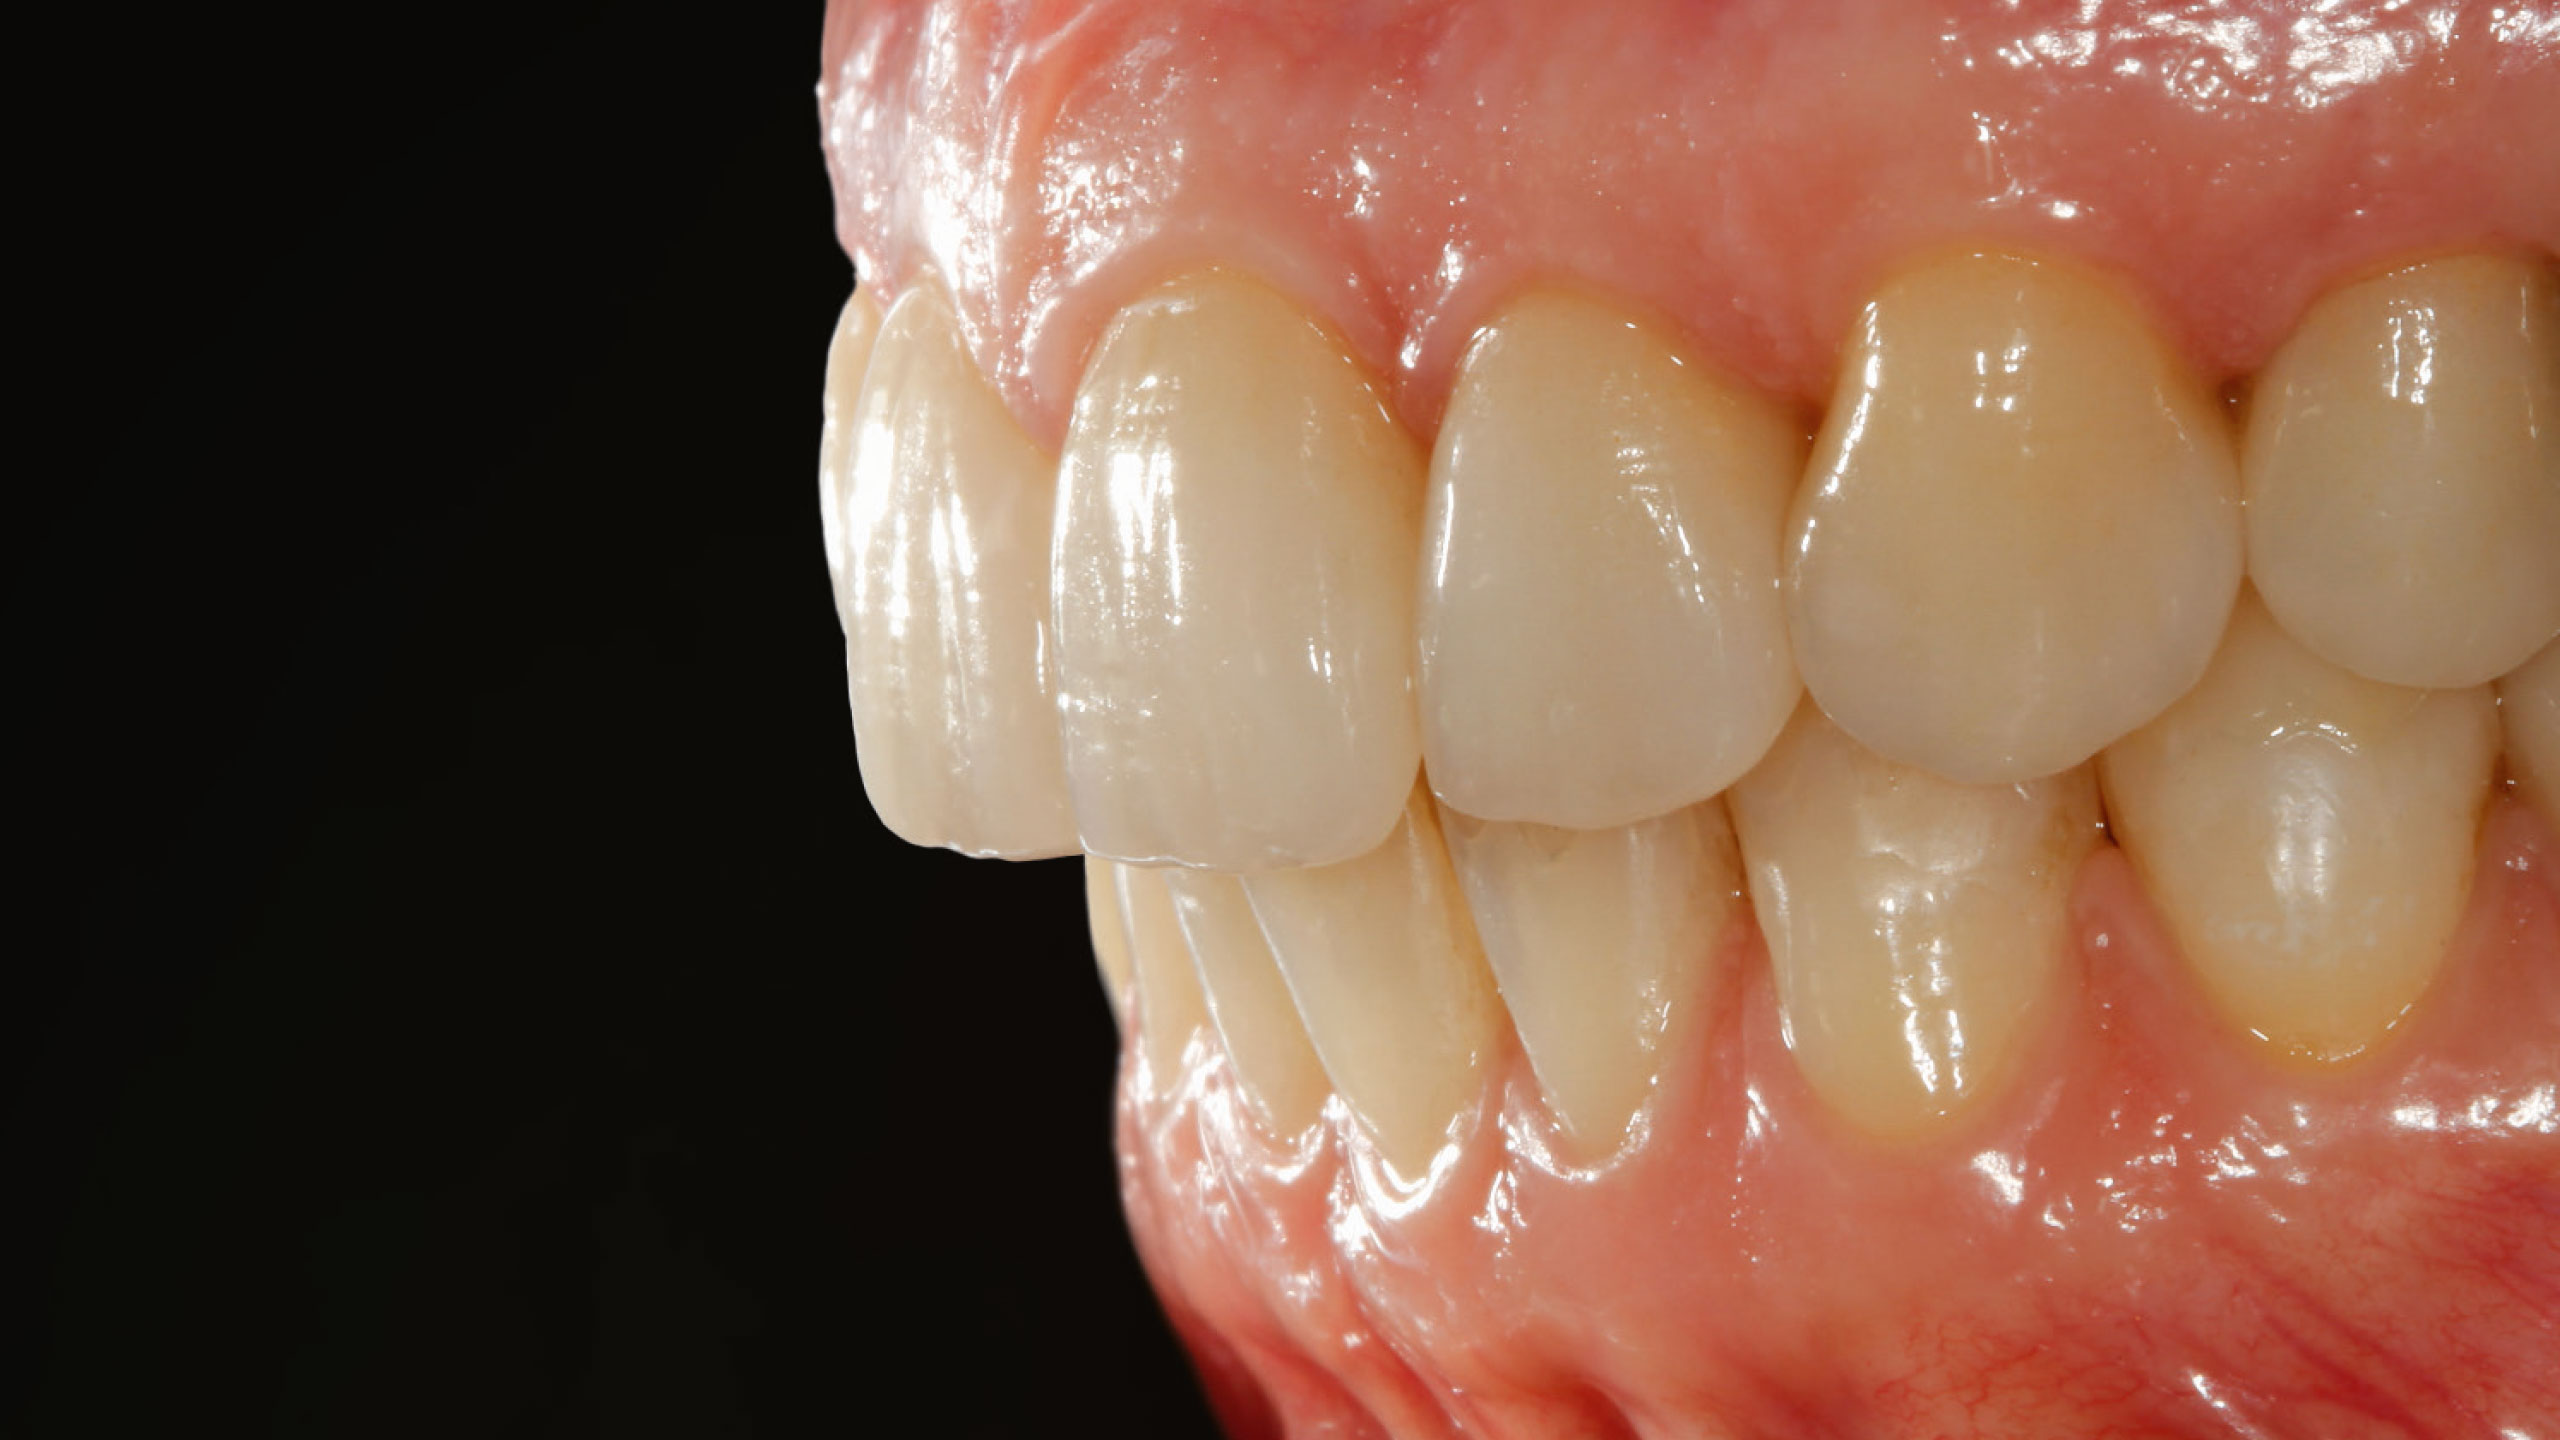

Im Labor konnten die vollkeramischen Restaurationen in der Presstechnik hergestellt werden (Abb. 8 bis 11). Die exakte Bisshöhe wurde zuvor im Mund evaluiert. Herstellung und Eingliederung der Veneers gestalteten sich dank des Wellenschliffs deutlich einfacher als mit anderen Veneer-Präparationsarten, da die Restaurationen am Zahn eine definierte Position hatten. Die adhäsive Eingliederung folgte den bekannten Abläufen. Die keramischen Restaurationen wurden geätzt beziehungsweise für das Verkleben konditioniert (Abb. 12). Nach dem Reinigen der Zähne wurden die Oberflächen mit Phosphorsäuregel vorbereitet, abgespült und getrocknet, mit Primer vorbehandelt, und es wurde Haftvermittler beziehungsweise Bonder aufgetragen (Abb. 13 bis 17). Nach dem Applizieren des Befestigungsmaterials konnten die Restaurationen eingegliedert und Materialüberschüsse entfernt werden (Abb. 18 und 19). Nach der Lichthärtung wurden die Ränder geglättet und die approximalen Kontakte angepasst sowie final poliert (Abb. 20 bis 24). Dabei zeigte sich ein weiterer Vorteil des Pfullinger Wellenschliffs. Der Übergang zwischen Zahn und Keramik ist dank des „diffusen“, bewusst unregelmäßig angelegten Präparationsdesigns optisch kaum wahrzunehmen. Eine Kontrolle der funktionellen Gegebenheiten bildete den Abschluss der prothetischen Therapie. Die in der Initialphase stabilisierte neue vertikale Bisshöhe konnte 1:1 mit den keramischen Restaurationen übernommen werden (Abb. 25).